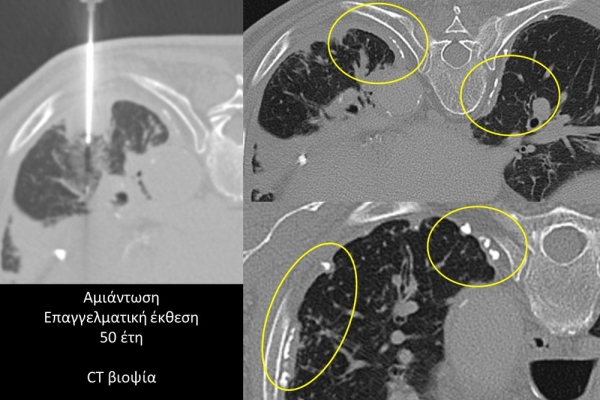

Η διαδερμική βιοψία είναι μία ελάχιστα επεμβατική μέθοδος λήψης υλικού από τον όγκο για κυτταρολογική και ιστολογική εξέταση, από εστιακές αλλοιώσεις του ήπατος, πνεύμονα, νεφρού κλπ. Συστήνεται από τον κλινικό ιατρό ανάλογα με το είδος και το μέγεθος της βλάβης και πραγματοποιείται με ασφάλεια από επεμβατικό ακτινολόγο με την καθοδήγηση αξονικού τομογράφου ή υπερήχων. Στη σύγχρονη ογκολογική θεραπεία όπου γίνεται προσπάθεια καταπολέμησης του καρκίνου σε μοριακό επίπεδο κρίνεται αναγκαία η ακριβής ιστολογική ταυτοποίηση του όγκου ώστε να εφαρμοσθεί εξατομικευμένη θεραπεία για το βέλτιστο αποτέλεσμα. Οι κατευθυνόμενες βιοψίες στοχευουν στο να παρέχουν στον κλινικό ογκολόγο το απαραίτο ιστοπαθολογικό υλικό που θα του επιτρέψει να εφαρμόσει την κατάλληλη θεραπεία για τον ογκολογικό ασθενή.